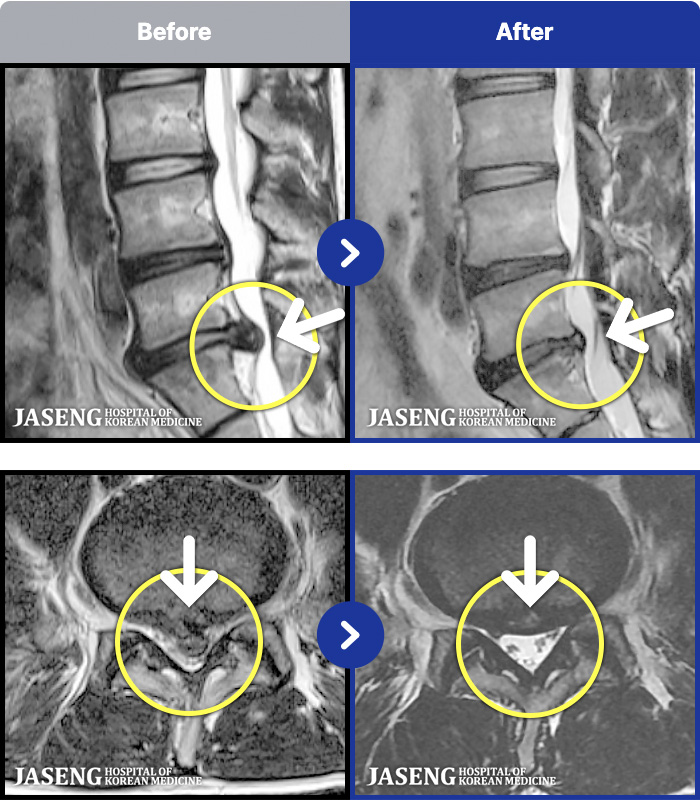

MRI ġ

[Կñ:21.12.17~22.07.04]

[_㸮ũ] 㸮

2026.01.09